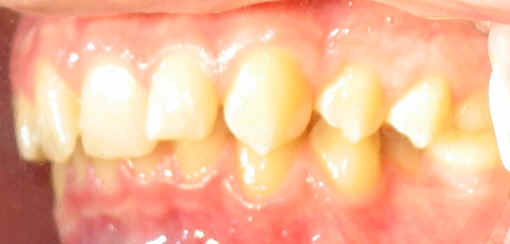

Malpositioned Premolar 13 year-old Caucasian boy

Pre-op 2009/04/18